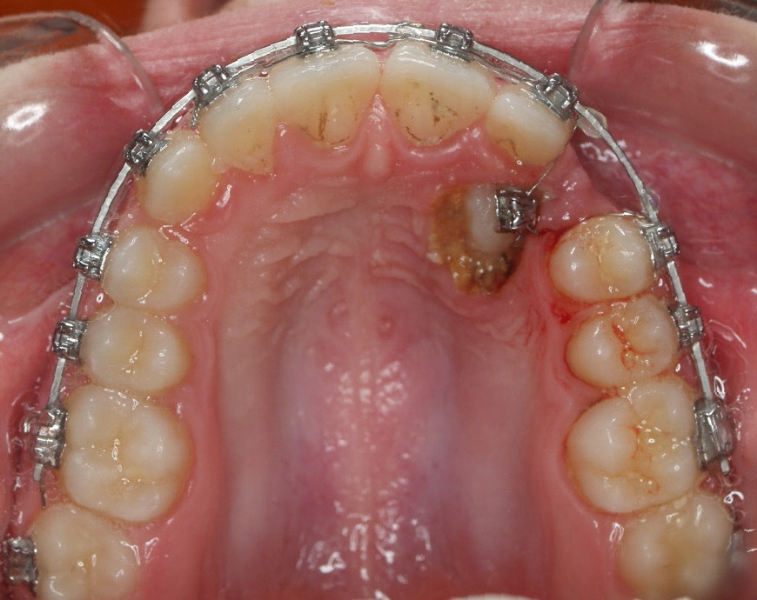

Clase II paciente 15 años

La paciente O.O. acude a nuestra consulta por:

– Canino 13 e incisivo lateral 42 en posición ectópica.

– Canino 23 incluido.

Con lo que decide realizarse un tratamiento de ortodoncia de duración de 24 meses con brackets damon Q.

CASO COMPLETO: